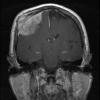

NEOPLASMS (MENINGIOMA)

Whorling-Sclerosing